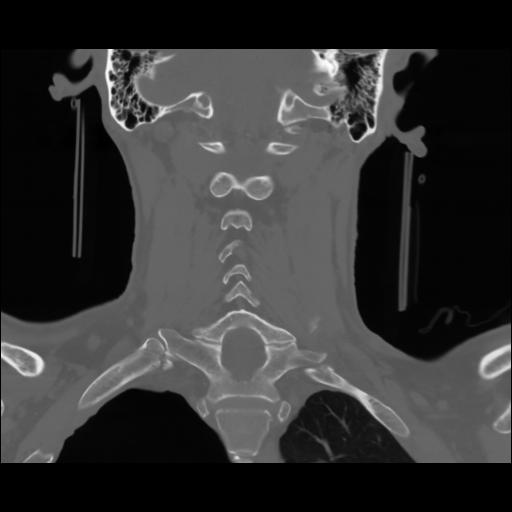

13 P.BLANDAS,,Coronal,2.000,P.BLANDAS,Coronal,